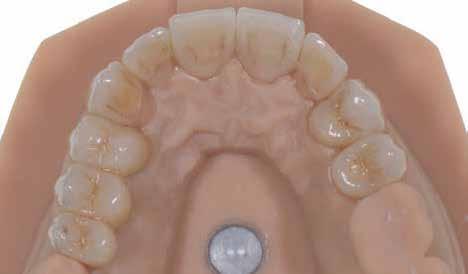

8. ábra. Az ultravékony héjak adhezív módszerekkel történő ragasztása. (A): Az elkészült héjak. (B): A fogfelszínek kofferdám izolálásban történő foszforsavas kondicionálása. (C): Az adhezív felvitele. (D): A héjak fényre kötő rezin alapú ragasztócementtel történő ragasztása.

ás, majd #0-ás retrakciós fonalakat (Ultrapak, Ultradent Products Inc, South Jordan, Utah, Egyesült Államok) helyeztünk. A végső precíziós lenyomatot polivinil-sziloxán lenyomatanyaggal (Virtual 380, Ivoclar Vivadent AG, Schaan, Liechtenstein) vettük. A fogtechnikai fázisban ultravékony (0,5 mm-nél vékonyabb) földpátkerámia héjak elkészítését kértük (Super Porcelain Ex-3, Kuraray Noritake Dental, Tokió, Japán), (7. ábra). A kerámia héjak készre vitelét követően a próba során a héjakat a helyükre illesztettük a széli zárást, az így kialakított fogformák ellenőrzése céljából. A páciens elégedett volt az így kapott látvánnyal. A végleges ragasztás kofferdám izolálásban történt. A preparált fogak felületét először 37%-os foszforsavval (Total Etch, Ivoclar Vivadent) 15 másodpercen keresztül kondicionáltuk, majd vízzel leöblítettük (8. ábra). A kondicionált zománcfelszíneket Adhese Universal (Ivoclar Vivadent) adhezívvel kezeltük. A kerámiahéjak homorú felszíneit 5%-os folysavval (IPS Ceramic Etching Gel, Ivoclar Vivadent) 20 másodpercen át kondicionáltuk, majd a felszíneket Monobond Plus primerrel (Ivoclar Vivadent) vontuk be (7. és 8. ábrák). A héjakat fényre kötő rezinalapú ragasztócement (Variolink Esthetic LC, Ivoclar Vivadent) applikálását követően a helyükre illesztettük. A kifolyó cementfelesleg eltávolítását követően minden felszínt (labiális, palatinális, meziális és distális) LED-es polimerizációs lámpával (VALO Cordless, Ultradent) 40 másodpercen keresztül megvilágítottuk.